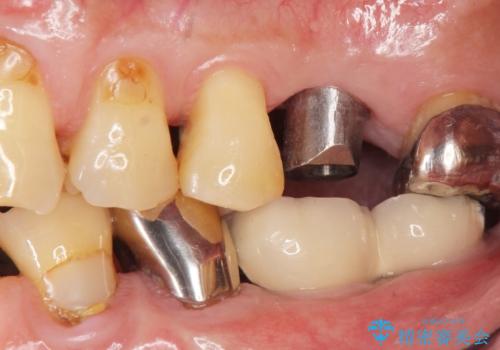

奥歯のインプラント ソケットリフト 60代男性

- 奥歯のインプラントをご希望し、来院された患者様です。

精査したところ上顎骨の厚みが薄かったため、ソケットリフト(上顎洞底挙上術)を併用してインプラント治療を行いました。

審美的・機能的な仕上がりに喜んで下さいました。

また、半年という比較的短期間でインプラント治療が終わったことにもご満足頂けました。

インプラントの種類:スプライン ツイスト (保証期間:5年)

クラウンの種類:ベレッツァクラウン (オールセラミック)

固定様式:セメント固定